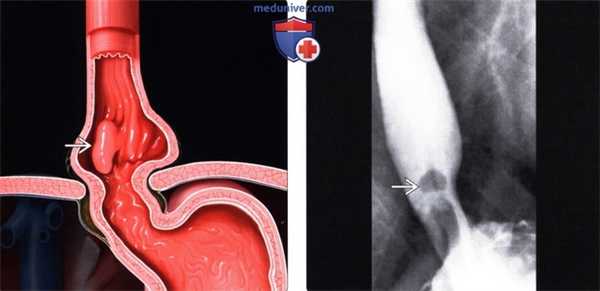

Гиперпластический полип у мужчины 45 лет.

На рентгенограмме визуализирован персистирующий узелок со сравнительно ровными контурами (указатели) в дистальном отделе пищевода около желудочно-пищеводного перехода (а).

При эзофагогастродуоде-носкопии (ЭГДС) (6) выявлен полип (стрелки) размером около 2,5 см, пациенту была проведена эндоскопическая резекция слизистой оболочки.

При гистологическом исследовании обнаружены грануляционная ткань и гиперплазия фовеолярного эпителия, что характерно для гиперпластических полипов. Подслизистый полип пищевода у мужчины 70 лет.